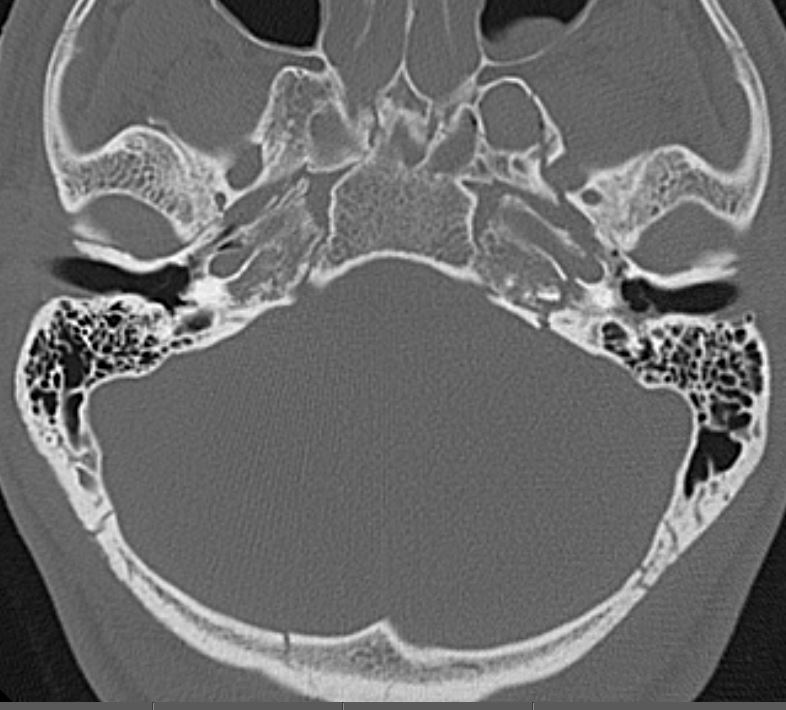

Right Temporal Bone

The inner ear including the lateral semicircular canals, vestibule and/or cochlea is fractured or otherwise abnormal.

Left Temporal Bone